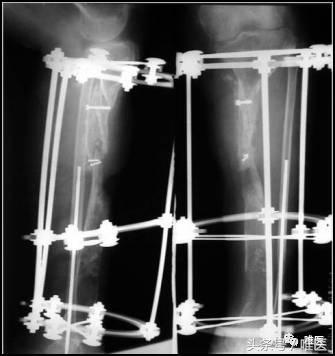

6. 手术方案

一期:左胫骨全环外架固定,远端截骨,术后骨段逐渐滑移,克服骨缺损。

二期:一期术后6个月,两骨断端逐渐靠近、重叠到位后,再行左胫骨中上段断端修整、重叠对合,髂骨植骨螺钉固定,继续外架保护固定。